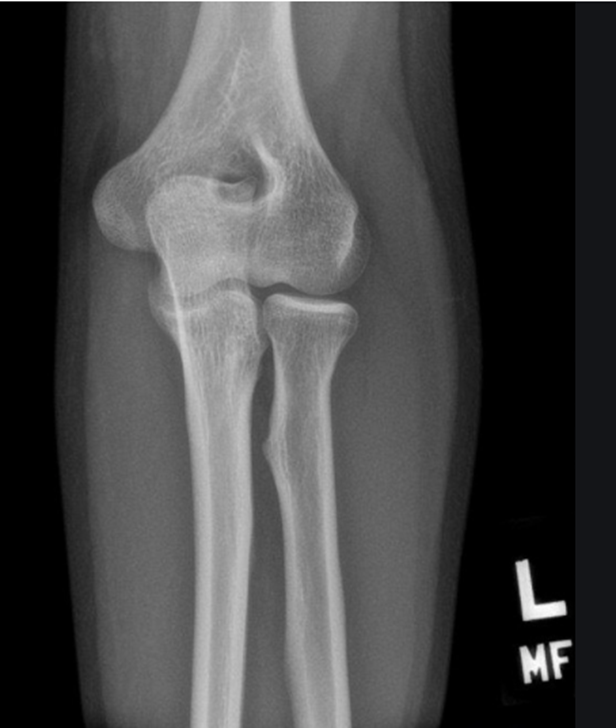

-All anatomy present

-Collimation is tight, want to open up some more

-Totally body positioning was not utilized because you cannot see the 3 concentric arches (trochlear notch, trochlear sulcus, ridges of the capitulum and trochlea)

-Not fully bent 90 degrees but close

-Coronoid process and radial head should be half superimposed (this image is a little more than half)

-Olecranon is in profile

-No marker

-REPEAT cause not in a true lateral position

Critique this lateral elbow image